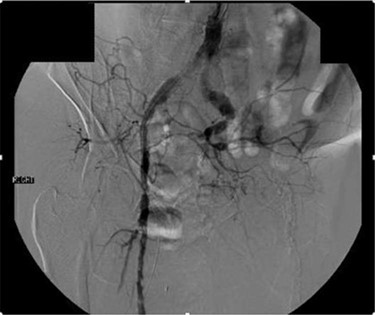

Workup began with noninvasive studies of the left lower extremity displaying aortoiliac occlusive disease and infrainguinal disease. Aortogram demonstrated a severely calcified aorta, patent left common iliac and proximal hypogastric arteries, with occlusion of the left external iliac, left common femoral and left superficial femoral arteries (Fig. 1). The right iliac system was patent apart from an occluded right hypogastric artery. A selective left lower extremity angiogram demonstrated reconstitution of the mid-to-distal profunda femoris artery (Fig. 2) to the proximal above-knee popliteal artery at the adductor hiatus (Fig. 3). Extensive collateralization was appreciated in the pelvis and lower extremity, between the residual left hypogastric artery and profunda femoris artery. Endovascular revascularization attempts were unsuccessful.

Aortogram demonstrating occlusion of left distal hypogastric, external iliac and common femoral arteries, as well as right hypogastric artery